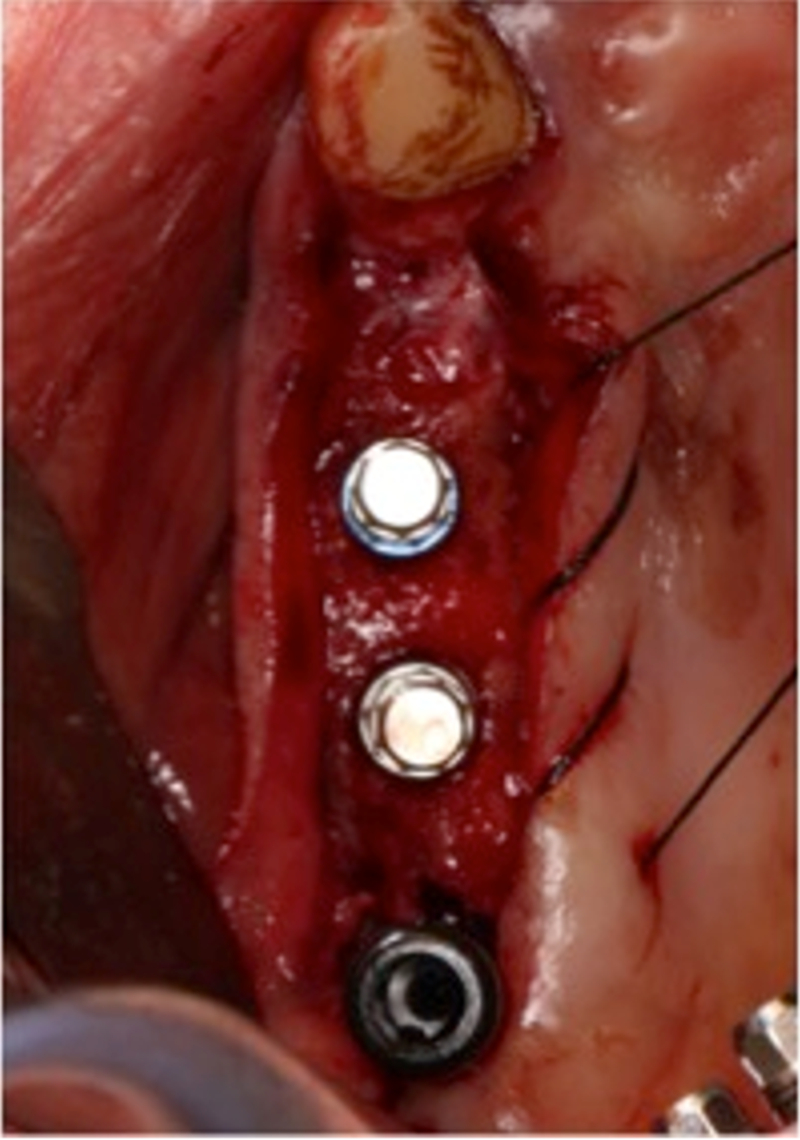

®按照術前方案進行備洞及植體植入

®按照術前方案進行備洞及植體植入,醫(yī)生可以通過屏幕軟件引導對手術中植入點、角度、深度實時追蹤

®對植體深度及方向進行確認

®完成3顆植體的植入,植體位點如術前方案設計,均在同軸線。